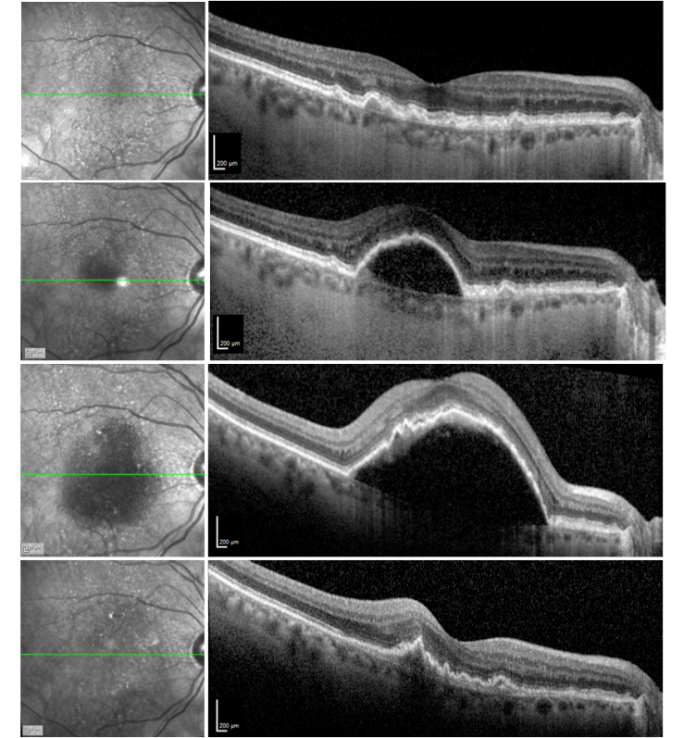

Corrected ETDRS visual acuity in the right eye declined from 20/32 to 20/64-2. Intravitreal therapy with aflibercept was instituted monthly for three consecutive months. After three injections, corrected ETDRS visual acuity remained 20/64, and the PED had increased significantly in size (Figure A). Given the recalcitrant nature and height of the PED, combination therapy with an intravitreal corticosteroid, specifically an intravitreal 0.7 mg dexamethasone implant (OZURDEX), along with repeat intravitreal aflibercept was administered. One month later, the PED had resolved (Figure B). Intraocular pressure was 19 mmHg. Visual acuity remained 20/64.

Figure: Heidelberg Spectralis spectral domain optical coherence tomography image of the right eye. All scans are horizontal foveal scans. A) One month prior to development of pigment epithelial detachment (PED), drusen are apparent. B) Development of large PED, maximum vertical dimension 289 μm. C) After three monthly intravitreal aflibercept injections., the PED was significantly increased with a maximum vertical PED dimension 630 μm. D) One month after intravitreal 0.7 mg dexamethasone implant (OZURDEX) combined with repeat intravitreal aflibercept injection, the PED resolved. Visual acuity remained 20/64.